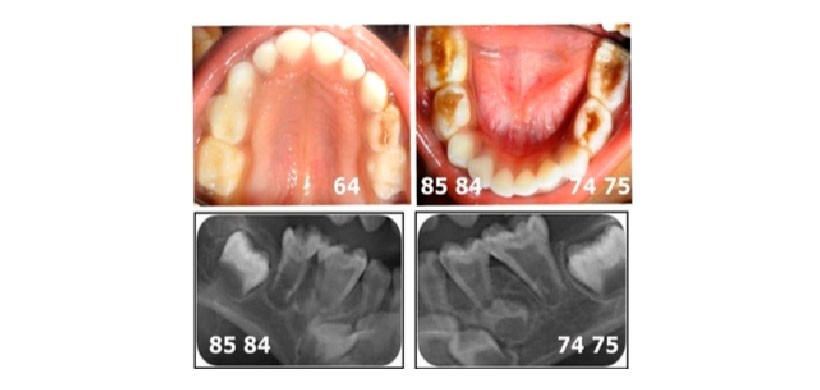

Figura 4: Radiografías periapicales luego de los tratamientos pulpares y de la rehabilitacion de las piezas dentarias con coronas protésicas.